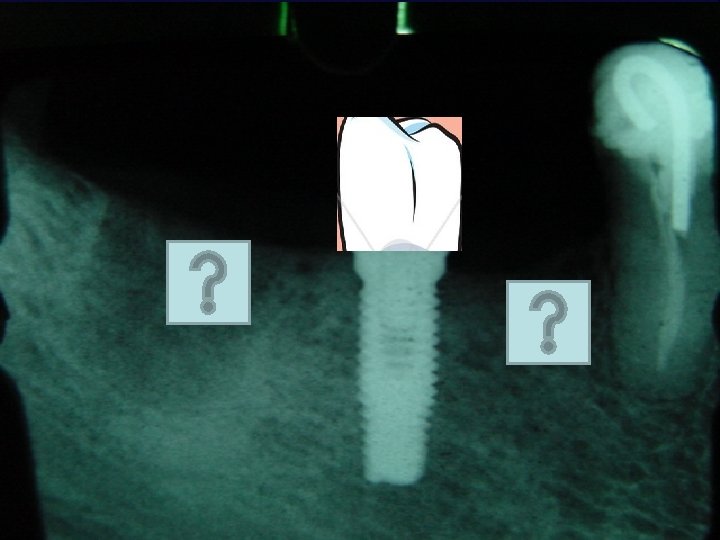

IMPLANTE: DOR: “ Onde há dor há fracasso” Fixação Rígida: mobilidade Horizontal pós carga Mobilidade horizontal pré-carga Mobilidade vertical Profundidade com Sonda: subjetivo; mais de 6 mm favorece infecção. Perda Óssea: rx inicial, quantificar perda óssea – crista alveolar referencial. Índice de Sangramento: subjetivo

IMPLANTE: Índice de Sangramento: subjetivo Doença Periimplantite: GUNA, placa dental, medicamentosa, hormonal PERIOIMPLANTITE. Percussão: Subjetivo ; só para avaliar dor Avaliação Radiográfica: crista óssea

IMPLANTE: “ Quando houver mobilidade horizontal maior do que 1 mm, qualquer mobilidade vertical, rápida perda óssea progressiva, dor a percussão, dor a função”. MISCH (1996 )